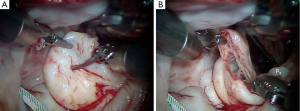

The redundant, large P2 segment is best evaluated using ventricular saline pressure filling (saline test) (Figure 2). The height (length from annulus) of P1 and P3 are used to guide the ultimate length of the remaining P2 segment. The end of P2 is resected horizontally (by the ‘haircut’ technique) to approximate the length of P1 and P3 (Figure 3). Any stable chords of good quality attached to P2 are identified and preserved along with a small leaflet segment. We propose three scenarios to reconstruct P2 during the leaflet-plasty.

Scenario 1: straight ‘haircut’ resection with primary chord reimplantation

In the presence of a widely flail, large P2 from a great number of ruptured chords, this technique works well (Figure 4A) (3). As seen in Figures 3,4B, the tip of P2 is divided horizontally using the height of P1 and P3 as a comparative guide. Thereafter, intact primary or secondary chords are reimplanted along the ‘new’ edge of P2 (Figure 4C). By bringing more lateral primary chords toward the center of P2, any residual prolapse becomes reduced. At this time, ‘clefts’ between P1 and P2 or P2 and P3 can be closed, adding additional chordal support to P2. An appropriately sized flexible annuloplasty band or ring have been implanted in all of our mitral repairs using interrupted 2-0 braided mattress sutures (Figure 4D). Currently, to save cardiac arrest time and provide a secure band attachment, we use the Cor-Knot™ suture-fastening device (LSI Industries, Inc., Victor, NY). The band shortens the posterior annulus and displaces it anteriorly, creating greater leaflet coaptation. A final coaptation surface of 8-10 mm is ideal. A saline test should be done to demonstrate both valvular competence and P2 prolapse reduction.